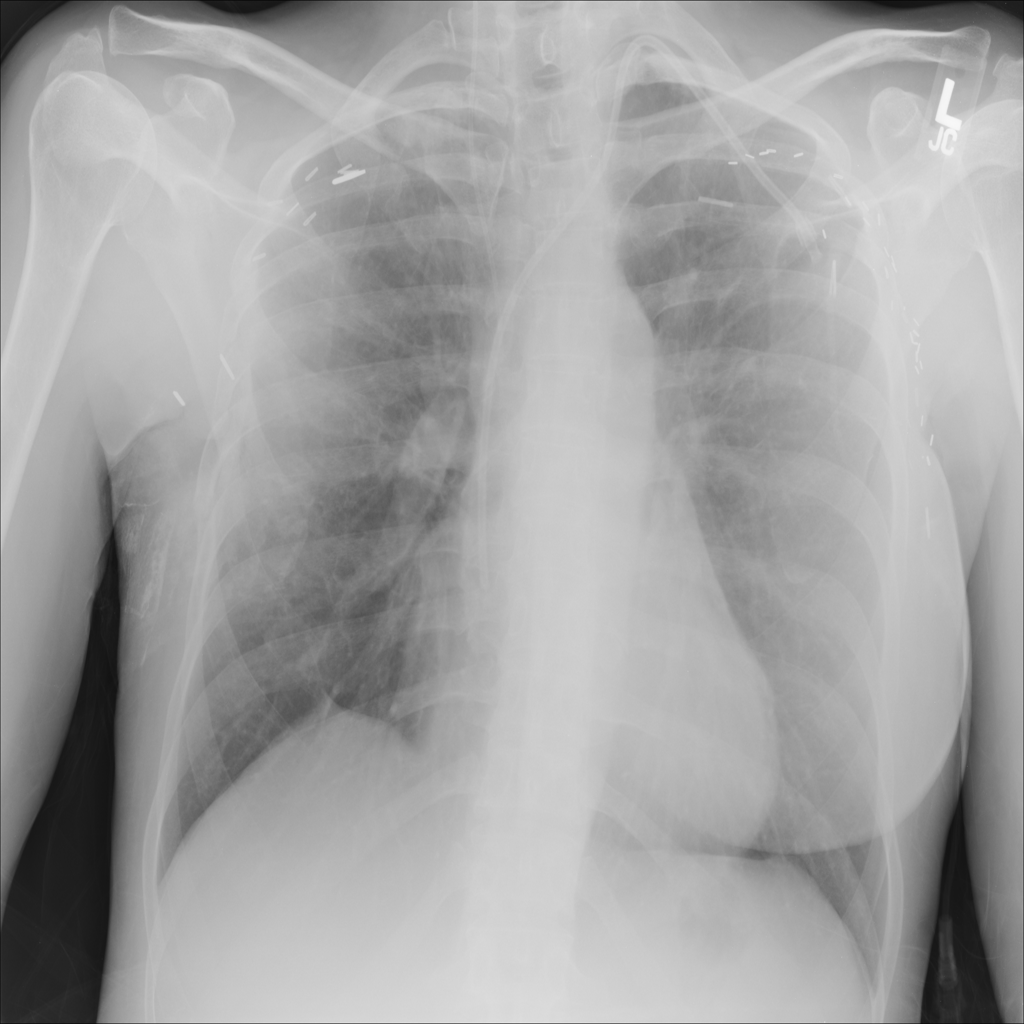

PAT-D7A5 · IMG-000Mass

PAT-D7A5 · IMG-000

PA